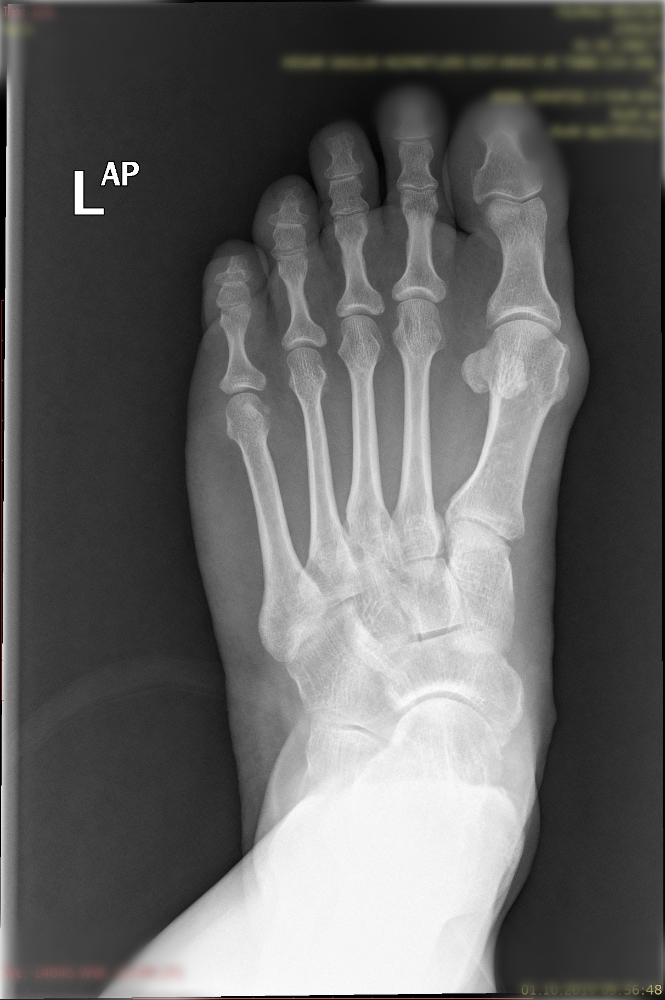

Halluk valgus ayak baş parmağının zaman içerisinde değişik nedenlerle eğilmesi ile ayak yan tarafında çıkıntının da eşlik ettiği bir rahatsızlıktır. Sıklıkla bayanlarda görülmesine rağmen erkeklerde ve çocukluk yaşlarında da karşılaşılmaktadır. Ayağın yan tarafında olan çıktı ve baş parmağın diğer parmakları itmesi ile ayakta şekil bozukluğu ve ağrı oluşur. Bu şekil bozukluğu kişinin ayakkabı giymesinde sıkıntılara neden olabilir.

Tedavisinde ayağın yük veriri pozisyonda çekilen grafileri üzerinde yapılan ölçümlerden sonra hastanın yaşı ve aktivite seviyesine göre kişiye özel planlanmaktadır. Erken dönemlerde ayakkabı modifikasyonu, parmak arası makarası ve gece ateli kullanılmaktadır. Cerrahi gerekliliğe hastanın deformitesinin büyüklüğüne ve hastanın taleplerine göre karar verilmektedir.

Aşağıdaki grafiyi öncesi sonrası şeklinde görmek için farenizi sağ sola hareket ettiriniz.

Yukarıdaki grafileri daha net ve büyük görmek için üzerine tıklayabilir. Sağ üst köşedeki + - tuşları ile daha da büyütebilirsiniz.